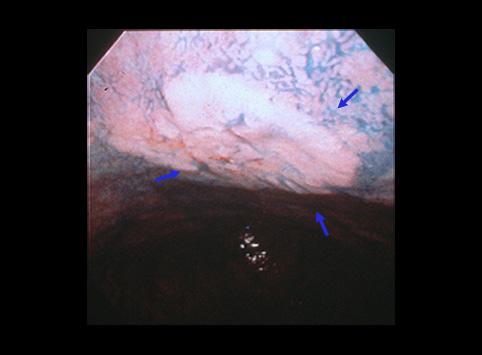

疾病(病理主体)的分类恶性上皮性肿瘤/腺癌

部位(按器官分)胃(部位)/体部

检查方法内窥镜

肿瘤的肉眼分类0型(表在型)/IIc型(IIc)

肿瘤最大直径15~19

肿瘤的深度sm